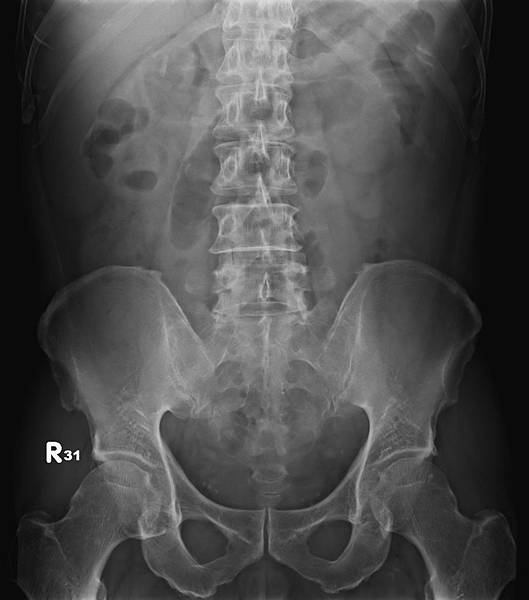

KUB看不出她的病有多嚴重: